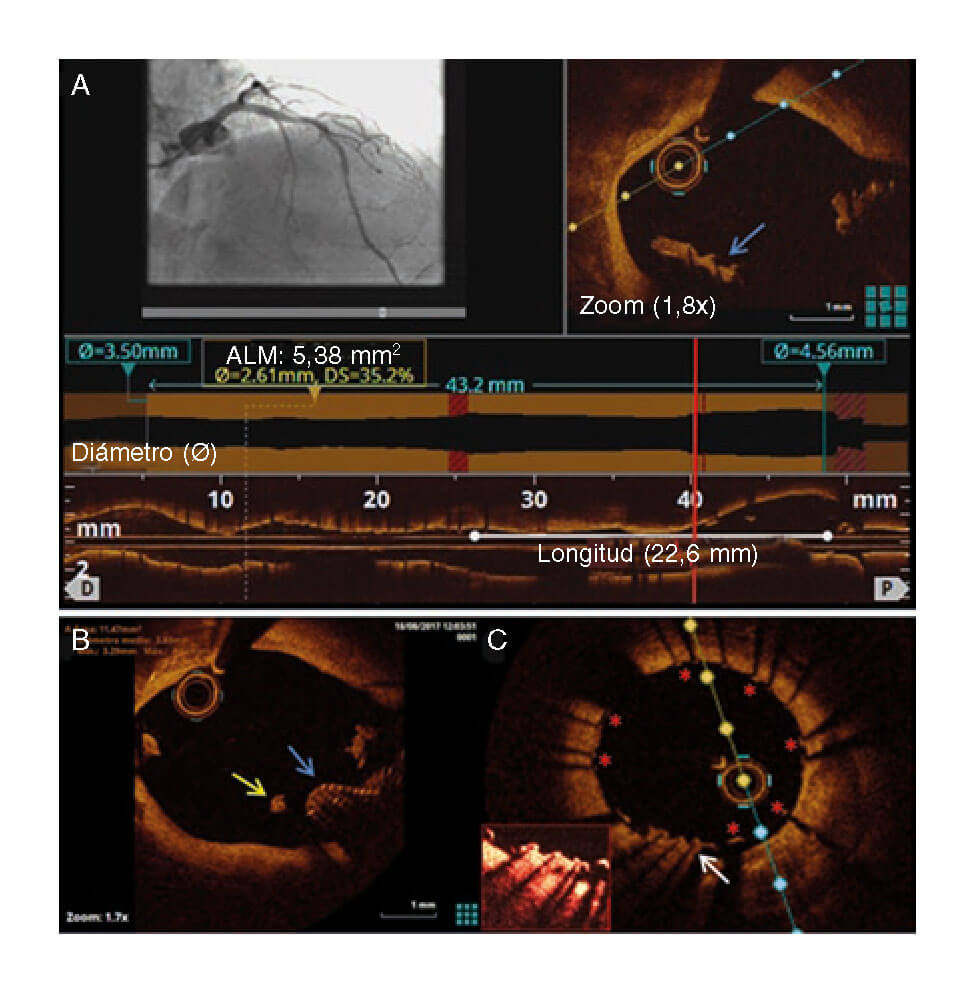

Después de implantar sin complicaciones un SFA en la DA media, se realizó una tomografía de coherencia óptica (OCT). La reconstrucción tridimensional llevada a cabo confirmó la presencia de restos de la guía rota (figura 2; flechas azules) saliendo de la Cx (figura 2; asterisco amarillo) y entrando en el tronco coronario izquierdo (TCI) y en la DA proximal y con material trombótico adherido y flotando libremente, tal y como revelan los cortes transversales (figura 3A y figura 3B; las flechas azules apuntan a los restos de la guía; la flecha amarilla, al material trombótico; ALM, área luminal mínima; vídeo 2 del material adicional). Se procedió a eliminar inmediatamente los filamentos deshilachados y a implantar un SFA en el TCI distal y en la DA proximal. La OCT de control confirmó el atrapamiento de la guía por los struts del stent contra la pared del vaso (figura 3C; flecha blanca: restos de la guía, resaltado en la caja remarcada en rojo; asteriscos rojos: struts del stent).

Figura 3